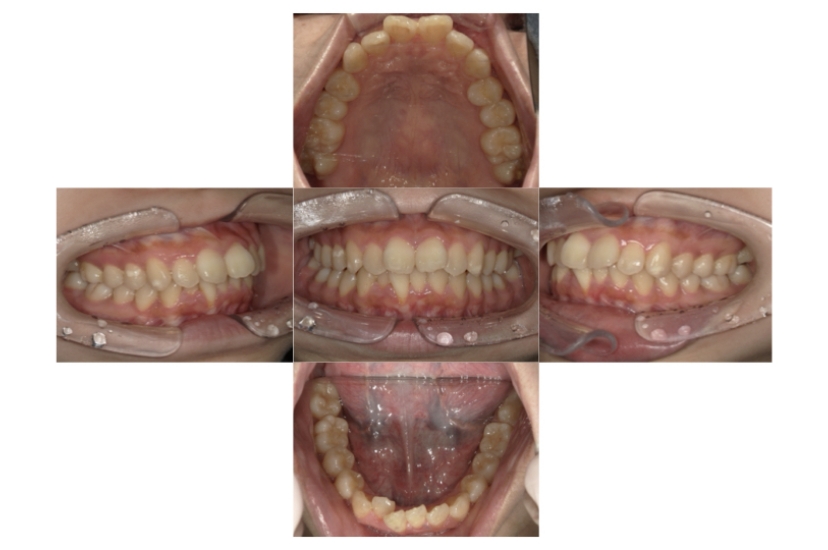

BEFORE

AFTER

症例4

下顎前突、叢生

抜歯

ブラケット矯正

上下顎叢生、反対咬合(上下の前歯のガタガタ、若干受け口)のケースです。

装置はラビアル(上下表側)で、上下顎の小臼歯を4本抜歯を行っています。抜歯したスペースを使って、上下の叢生改善と前歯の受け口の改善を行っています。

主訴 前歯のガタガタを治したい。

年齢・性別 45歳 女性

お住まいの地域 神奈川県川崎市

治療方針 抜歯スペースを利用して上前歯の叢生(ガタガタ)の改善と受け口の改善

抜歯部位 上顎左右第一小臼歯、下顎左右第二小臼歯

使用装置 ラビアル(上下表側)、顎間ゴム

治療期間 2年6か月

治療回数 20回

リテーナー クリアリテーナー